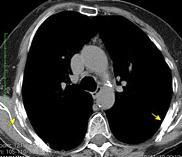

Masa axilar izquierda y derrame pleural derecho. Implantes pleurales, paraespinales . Ganglios en mamaria interna. Linfoma B difuso

Linfoma NH de cél. B. Invasión Transtorácica.

Afectación axilar